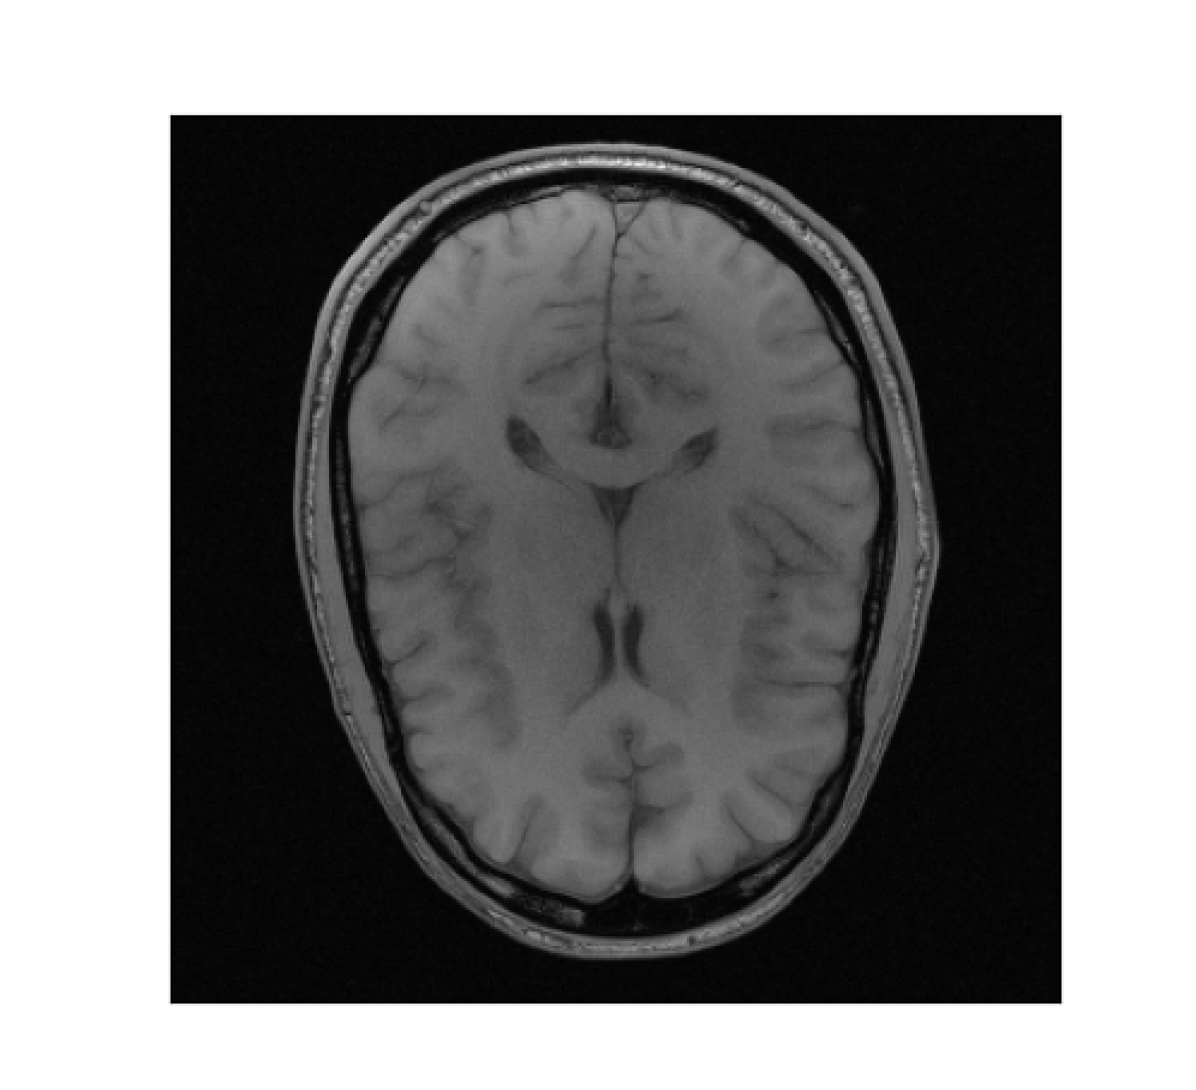

III-B2 Qualitative results

For visual inspection, we present the results of image reconstruction from data undersampled using SPARKLING trajectories generated for various target densities in Fig. 3 (T1subscriptT1\text{T}_{1}-w images) and Fig. 4 (T2subscriptT2\text{T}_{2}-w images). For the sake of space, we only report the best reconstruction results, i.e. with NC-PDNet. For T1subscriptT1\text{T}_{1}-weighted contrast, we show that all methods give similarly performing results, however 𝝆vdssubscript𝝆𝑣𝑑𝑠\boldsymbol{\rm\rho}_{vds} and 𝝆lbsubscript𝝆𝑙𝑏\boldsymbol{\rm\rho}_{lb} provide the best SSIM scores. Further, we observe that in this case, 𝝆vdssubscript𝝆𝑣𝑑𝑠\boldsymbol{\rm\rho}_{vds} is slightly better than 𝝆lbsubscript𝝆𝑙𝑏\boldsymbol{\rm\rho}_{lb}. On the contrary, for T2subscriptT2\text{T}_{2}-w contrast, 𝝆lbsubscript𝝆𝑙𝑏\boldsymbol{\rm\rho}_{lb} outperforms the other densities as reflected both visually in Fig. 4 and quantitatively (see Fig. 2).

Reference T1subscript𝑇1T_{1}-w Image (i) 𝝆vdssubscript𝝆𝑣𝑑𝑠\boldsymbol{\rm\rho}_{vds} (ii) 𝝆sbsubscript𝝆𝑠𝑏\boldsymbol{\rm\rho}_{sb} (iii) 𝝆lsbsubscript𝝆𝑙𝑠𝑏\boldsymbol{\rm\rho}_{lsb} (iii) 𝝆lbsubscript𝝆𝑙𝑏\boldsymbol{\rm\rho}_{lb}

Refer to caption Refer to caption Refer to caption Refer to caption Refer to caption

Figure 3: NC-PDNet-based image reconstruction for retrospective T1𝑇1T1-w imaging with slice 666 in file_brain_AXT1_201_6002725.h5 from validation data in fastMRI dataset for different target sampling densities.